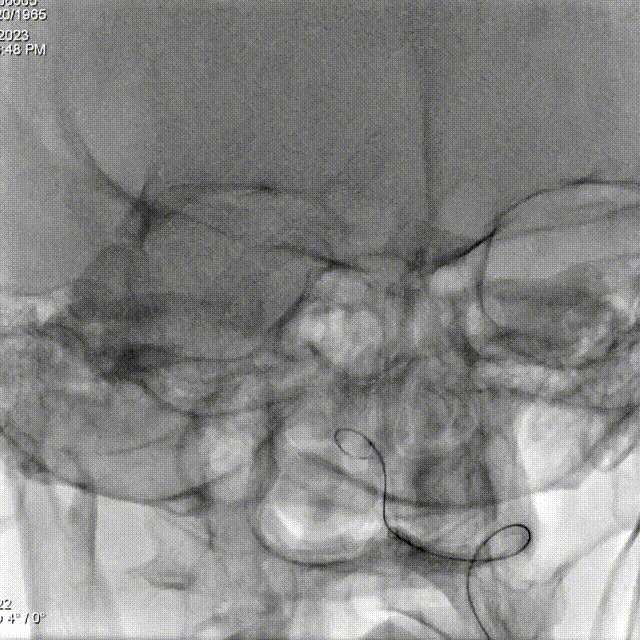

微导管到位:

Lattice支架输送:

Lattice血流导向密网支架 5.3mm*41mm输送到位。

Lattice血流导向密网支架 5.3mm*41mm头端释放。

Lattice支架头端定位:

造影确认支架头端位置。

重回收调整支架头端定位。

Lattice支架中段释放:

造影确认支架头端避开PCA。

继续释放支架中段。

Lattice支架近端释放:

造影确认支架打开贴壁良好。

Lattice支架完全释放:

解脱前造影。

撤微导管完全释放。

Lattice支架后处理:

J型导丝按摩。

术后即刻造影。